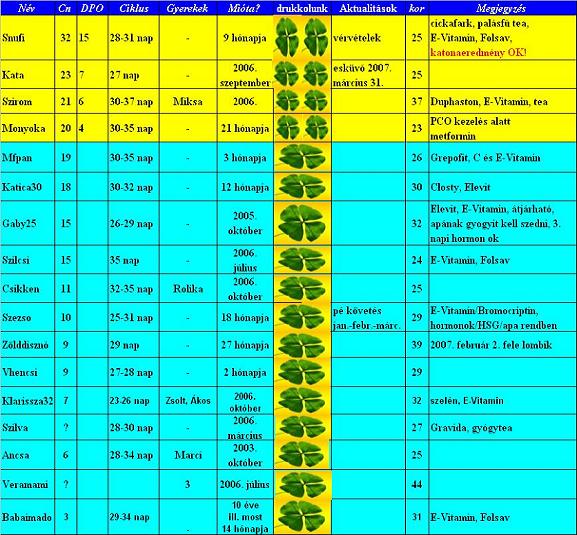

Szezso